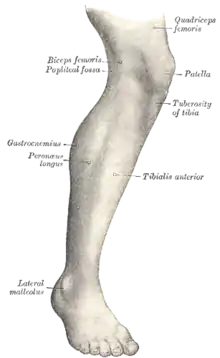

La maladie d'Osgood-Schlatter est une affection du genou ; c'est une apophysose aussi appelée « ostéochondrose tibiale antérieure » puisqu'il s'agit d'une souffrance de l’insertion basse du tendon rotulien au niveau de la tubérosité tibiale antérieure. La douleur résulte de microtraumatismes répétés exercés sur le tissu cartilagineux de croissance de la tubérosité tibiale antérieure par l'intermédiaire du ligament rotulien. Elle touche principalement l'enfant sportif, et se manifeste par une douleur de la face antérieure du genou. La maladie a été décrite en 1903 par les Drs Osgood et Schlatter, chacun de leur côté.

L'examen clinique suffit à assurer le diagnostic. Initialement l'enfant présente une boiterie après le sport. Puis la douleur peut s'intensifier et devenir permanente, présente même au repos. La douleur siège à la face antérieure du genou, au niveau de la tubérosité tibiale antérieure (TTA). À la palpation, celle-ci est tuméfiée, sensible voire douloureuse. Le genou lui-même, ainsi que la rotule, sont indolores[2].

Une radiographie n'est pas nécessaire notamment lorsque le tableau clinique est évocateur et que les douleurs sont bilatérales. Elle peut être utile pour éliminer une autre pathologie si les douleurs sont unilatérales, atypiques ou rebelles au traitement. Initialement on retrouve un soulèvement de la tubérosité tibiale antérieure avec élargissement de son cartilage de croissance ; dans les stades plus évolués, la TTA est fragmentée et on peut voir parfois des calcifications dans le ligament rotulien[2].